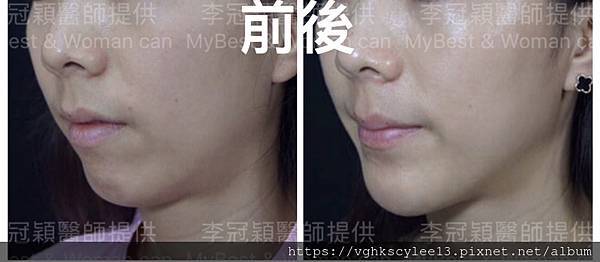

上 圖注射填下巴

下圖案例:下巴整形打造V型臉的效果(客製化goretex複合式假體)

案例:下巴整形(客製化goetex下巴假體)